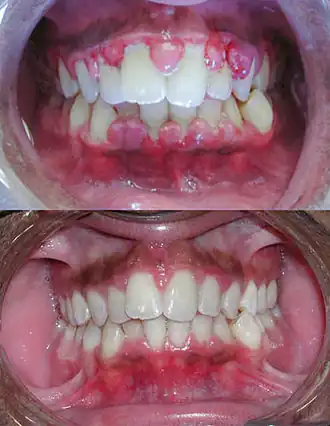

Gingivitis is een ontsteking (=itis) van de gingiva oftewel het tandvlees.

Gingivitis oftewel tandvleesontsteking ontstaat door de ophoping van tandplaque en tandsteen rondom tanden en kiezen. Het kenmerkt zich door roodheid en zwelling van het tandvlees. Tevens gaat het tandvlees bij aanraking gemakkelijk bloeden. Gingivitis kan genezen door een goede mondhygiëne toe te passen. Daarnaast kan een behandeling bestaan uit verwijdering van tandplaque en tandsteen door de tandarts.[1]